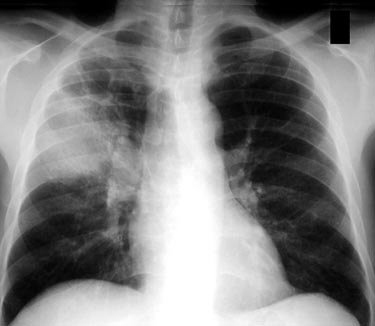

Расшифровка цифровых кодов флюорографии с примерами

01 - Кольцевидная тень (полость).

02 - Затемнение в легочной ткани (инфильтрация,ателектаз, округлая тень, среднедолевой синдром и др.).

03 - Очаговые тени в легочной ткани.

04 - Расширение тени средостения, в том числе увеличение размеров корня.

05 - Плевральные выпоты.

06 - Фиброзные изменения в легочной ткани (выраженные).

07 - Фиброзные изменения в легочной ткани (ограниченные).

08 - Повышение прозрачности легочной ткани (эмфизема локальная и распространенная).

09 - Изменения плевры (сращения, плевральные наслоения, обызвествления) выраженные.

10 - Изменения плевры (сращения, плевральные наслоения, обызвествления) ограниченные.

11 - Петрификаты крупные в легочной ткани - множественные (5 и более).

12 - Петрификаты крупные в корнях - множественные (5 и более).

13 - Петрификаты мелкие в легочной ткани - множественные (5 и более).

14 - Петрификаты мелкие в корнях - множественные (5 и более).

15 - Петрификаты крупные в легочной ткани - единичные.

16 - Петрификаты крупные в корнях - единичные.

17 - Петрификаты мелкие в легочной ткани - единичные.

18 - Петрификаты мелкие в корнях - единичные.

19 - Изменения диафрагмы, не связанные с плевральной патологией (диафрагмальная грыжа, высокое стояние диафрагмы и т. д.).

20 - Состояние после операции на легком.

21 - Изменения скелета грудной клетки (сколиоз, кифосколиоз, костная мозоль, добавочное ребро, остеофиты и т. д.).

22 - Инородное тело (проецируется на легочную ткань, тень средостения в мягких тканях).

23 - Сердечно-сосудистая патология.

24 - Прочие - добавочная доля.

25 - Норма.

26 - Брак.

Примечания:

При сочетании нескольких из перечисленных изменений каждое из них отмечается соответствующим кодом в каждой графоклетке.

Локализация, протяженность изменений отмечается дробью по второй графоклетке 1; 2; 3; 4; в числителе - правое легкое, в знаменателе - левое легкое (по полям).

Номер шифра легочных полей: 1 - первое, 2 - второе, 3 - третье, 4 - первое и второе, 5 - первое и третье, 6 - второе и третье, 7 - первое, второе и третье.

В третьей графоклетке вместо подписи врача подставляют личный номер рентгенолога.

Вызов на контрольное рентгеновское дообследование отмечается в четвертой графоклетке цифрой 1.